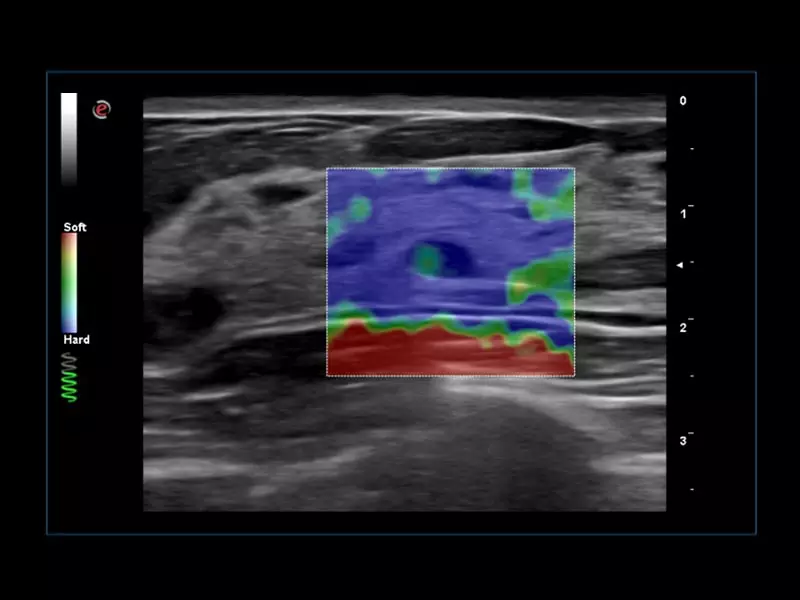

MyLab™C30 - SWE breast

MyLab™C30 - SWE breast

MyLab™C25 - ElaXto in breast

MyLab™C25 - ElaXto in breast

MyLab™9 Platform - Dual ElaXto characterization on breast lesion

MyLab™9 Platform - Dual ElaXto characterization on breast lesion

MyLab™9 Platform - Elastography advanced measurement package on breast lesion

MyLab™9 Platform - Elastography advanced measurement package on breast lesion

MyLab™X8 Platform - Lesion with ElaXto

MyLab™X8 Platform - Lesion with ElaXto

MyLab™X8 Platform - Stiffness quantification with Q-ElaXto

MyLab™X8 Platform - Stiffness quantification with Q-ElaXto